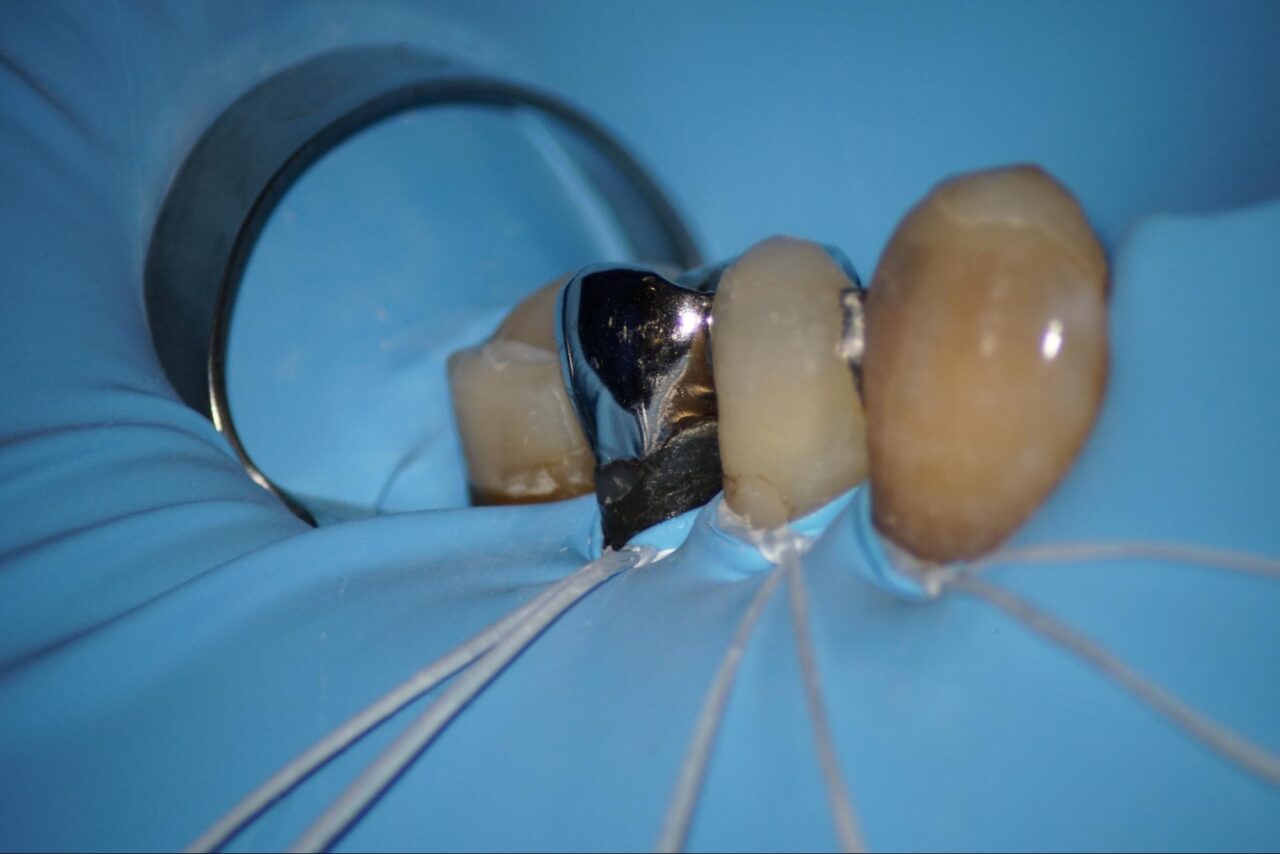

感染根管症例:術全から歯冠形態を作って初日終了まで

術前:麻酔をした後にラバーダムをしてクラウンを外します。

レジンコアの中にメタルのスクリューが入っているので除去します。

慎重に削って行きます。